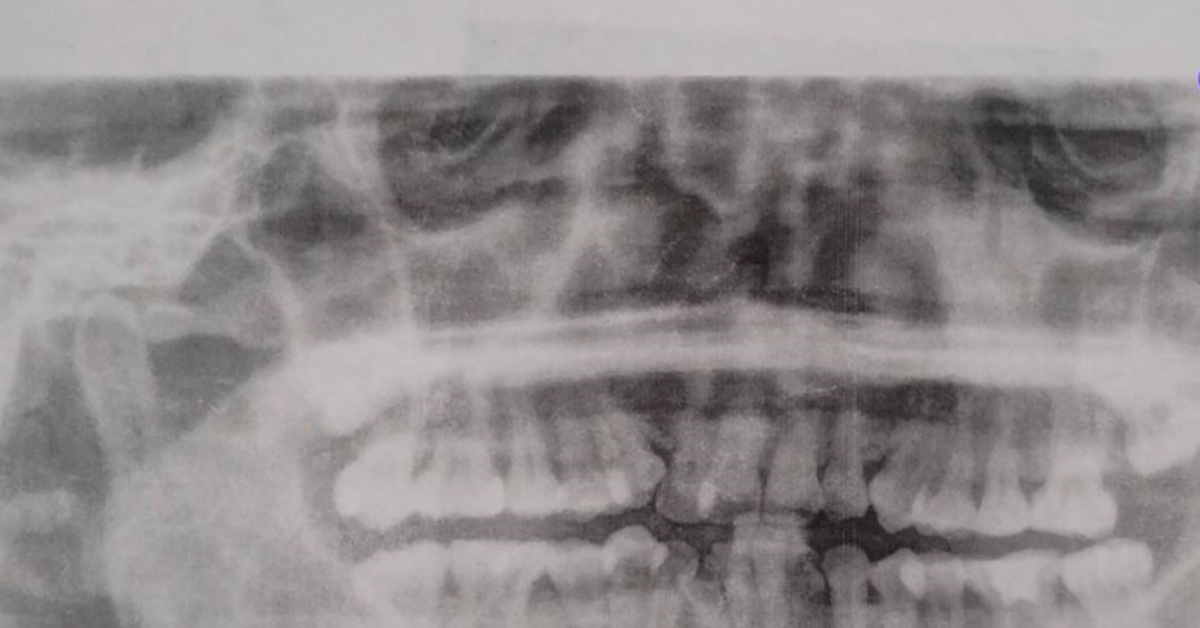

นางกฤติกา เล่าว่า เมื่อปี 2558 ได้ผ่าฟันคุดที่โรงพยาบาลใน จ.นราธิวาส ทันตแพทย์ลืมหัวกรอฟันไว้ในเหงือก และแจ้งว่าไม่เป็นไร หากแผลประสานกัน ชิ้นส่วนดังกล่าวจะหลุดไปเอง ต่อมาต้นปี 2562 นางกฤติกาไปรักษารากฟัน และเอกซเรย์พบว่า หัวกรอฟันยังติดอยู่ในเหงือก จนมีการอักเสบ จึงต้องผ่าออก แม้อาการดีขึ้น แต่ไม่หายขาด คือ มีอาการชาตั้งแต่กกหูขวาถึงริมฝีปาก ตอนนี้ชาเฉพาะริมฝีปาก ลิ้นชาแค่ปลายลิ้น แต่ลิ้นรับรสยังผิดปกติ หูขวาตึง ที่ผ่านมาได้ขอรับการเยียวยา และร้องเรียน สคบ. สำนักงานสาธารณสุขจังหวัดนราธิวาส แต่ไม่เป็นผล เตรียมยื่นฟ้องผู้บริหารกระทรวงสาธารณสุข เพราะต้องกู้หนี้ยืมสินมาเป็นค่าใช้จ่ายช่วงที่ต้องพักรักษาตัว และเป็นค่าเดินทางไปโรงพยาบาล เป็นเงินกว่า 200,000 บาท. – สำนักข่าวไทย